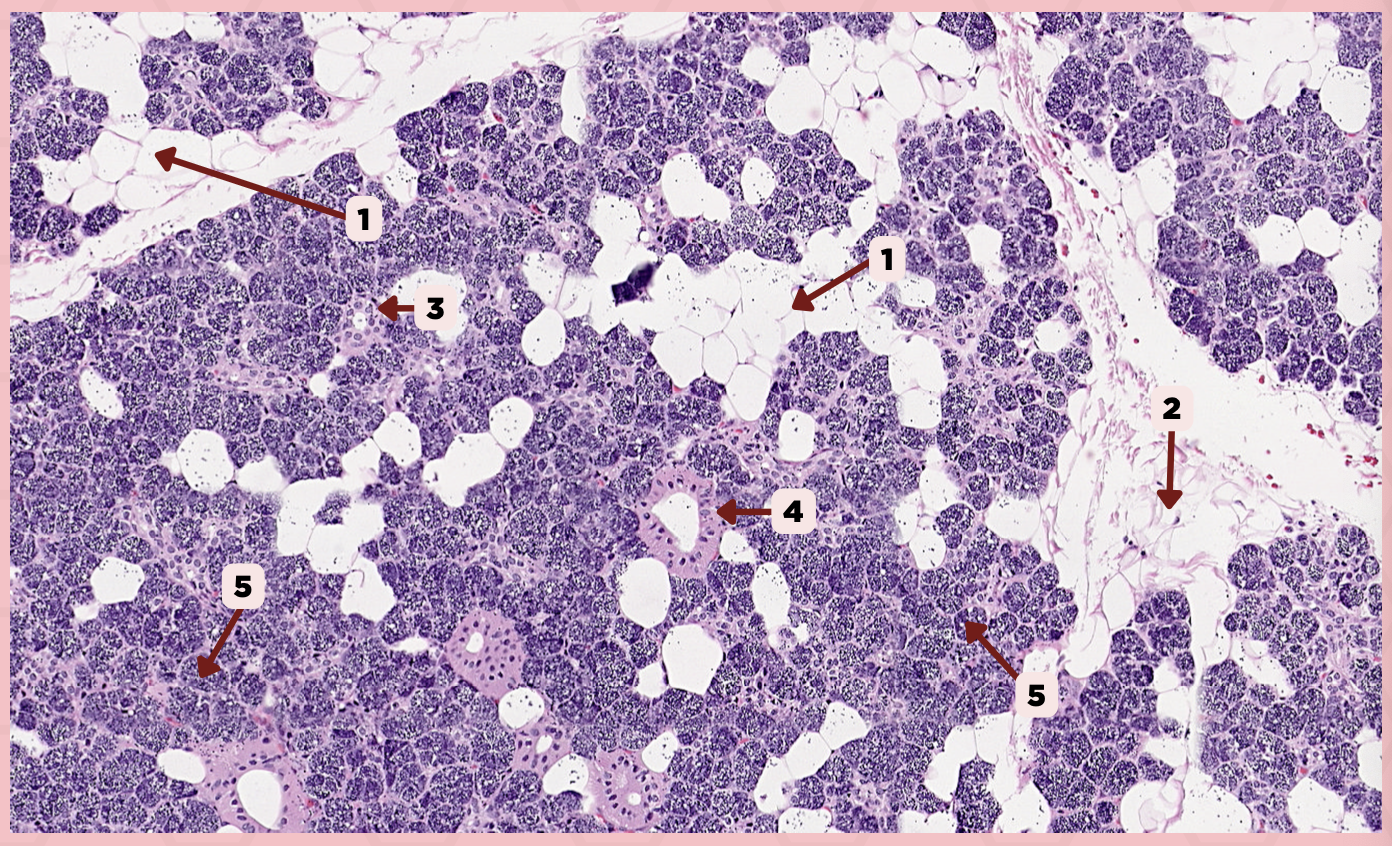

C) Adipocytes

The septa delineating the lobes and lobules contain a significant amount of:

A) Loose Connective Tissues

B) Myoepithelial Cells

C) Adipocytes

D) Reticular Tissue

Parotid

Identify the specimen.

Capsule

Identify the structure labeled as 1.

Lobule

Identify the structure labeled as 2.

Lobe

Identify the structure labeled as 3.

Connective Tissue

Identify the structure labeled as 4.

C) Striated Ducts

This duct exhibits intense cytoplasmic eosinophilia and basal striations when seen in routine LM preparations.

A) Intercalated Ducts

B) Excretory Ducts

C) Striated Ducts

D) Typical Serous Cells

The parotid gland is purely serous therefore its secretory units are exclusively formed by:

A) Nonkeratinized Cells

B) Myoepithelial Cells

C) Adipocytes

D) Typical Serous Cells

Parotid

Identify the specimen.

Adipocyte

Identify the structure labeled as 1.

Connective Tissue

Identify the structure labeled as 2.

Intercalated Duct

Identify the structure labeled as 3.

Striated Duct

Identify the structure labeled as 4.

Serous Gland

Identify the structure labeled as 5.